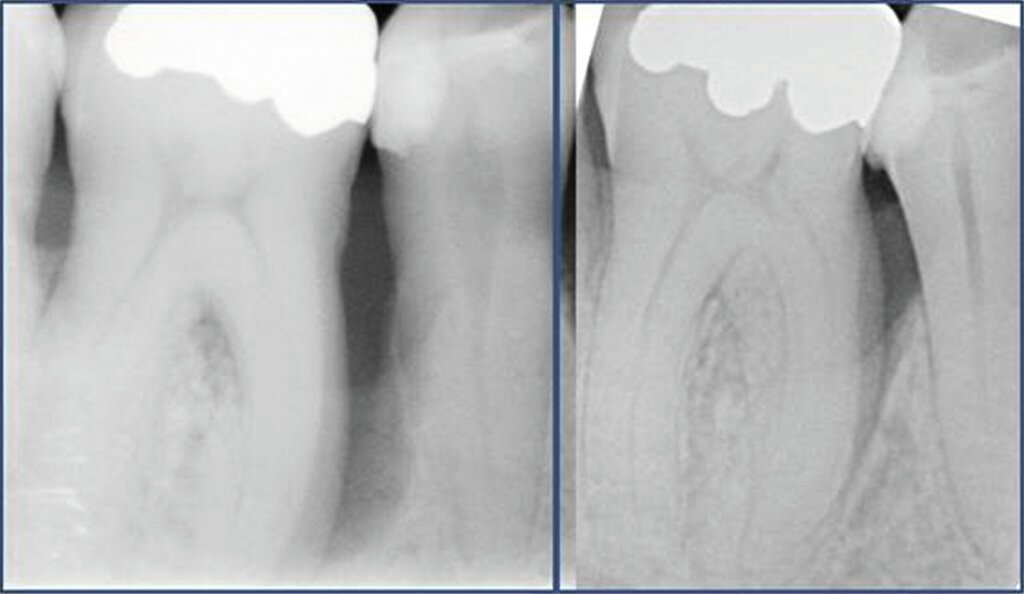

Die parodontale Regeneration ist eine gute Therapiemöglichkeit, um die Prognose von stark betroffenen Zähnen mit tiefen Resttaschen und Knochendefekten oder Furkationsdefekten zu verbessern. Der zusätzliche Nutzen für den Attachmentgewinn liegt bei durchschnittlich 1,34 mm und für die Reduktion der Sondierungstiefen bei 1,2 mm [Nibali et al., 2020]. Eine gute Plaquekontrolle wirkt sich dabei positiv auf das Heilungsergebnis aus und sollte deshalb die Basis für alle parodontalchirurgischen Maßnahmen sein [Rosling et al., 1976]. Auch Zähne mit Furkationsbefall sollten in die Parodontaltherapie einbezogen werden. Bei Furkationen von Unterkiefermolaren Grad II und Oberkiefermolaren mit bukkalem Furkationsbefund Grad II sollten regenerative parodontalchirurgische Maßnahmen in Betracht gezogen werden [Jepsen et al., 2020]. Zur Unterstützung der Regeneration von Knochentaschen oder Furkationsbefall Grad II stehen gut untersuchte Biomaterialien wie Membranen oder Schmelz-Matrix-Proteine mit oder ohne Zusatz von Knochenersatzmaterial zur Verfügung [Nibali et al., 2020]. Die Abbildungen 1 bis 3 zeigen einen Fall, bei dem durch eine regenerative Parodontalchirurgie die Prognose des Zahnes maßgeblich verbessert wurde.

Mehrere Studien berichten über gute Langzeitergebnisse nach dieser Therapieform, insbesondere auch bei primär „hoffnungslos“ eingestuften Zähnen [Cortellini und Tonetti, 2004; Pretzl et al., 2009; Nygaard-Østby et al, 2010; Cortellini et al., 2020; Sculean et al., 2008]. In einer Studie von Cortellini et al. [2020] wurden 50 Patienten mit je einem „hoffnungslos“ prognostizierten Zahn (Knochenabbau ad apex) entweder der Testgruppe (regenerative Behandlung) oder der Kontrollgruppe (Extraktion mit Implantation durch festsitzenden Zahnersatz) zugeteilt. Die Überlebensraten nach zehn Jahren betrugen 88 Prozent für die Test- und 100 Prozent für die Kontrollgruppe. Die Kosten der Therapie waren in der Testgruppe signifikant geringer. Auch wenn die Ergebnisse beeindrucken, ist kritisch anzumerken, dass alle Patienten im Zeitraum von zehn Jahren vierteljährliche Recall-Sitzungen erhielten und die Therapie in einer hoch spezialisierten Praxis durchgeführt wurde. Das heißt, dass diese techniksensitive Therapie in einer allgemeinzahnärztlichen Praxis nicht unbedingt den gleichen Erfolg erzielen würde. Dennoch zeigt die Studie, dass auch bei schwer erkrankten Zähnen noch Regenerationspotenzial besteht und man sich auf die erste prognostische Einschätzung nicht einhundertprozentig verlassen kann. Auch mit nicht-chirurgischer Parodontitistherapie und konsequenter Erhaltungstherapie konnten in einer weiteren Studie 88,2 Prozent der primär als fraglich und 59,5 Prozent der primär als hoffnungslos eingestuften Zähne über einen Zeitraum von 15 Jahren erhalten werden [Graetz et al., 2011]. Dabei ist häufig ein beachtliches regeneratives Potenzial allein durch die nicht-chirurgische Parodontitistherapie festzustellen (Abbildung 4).